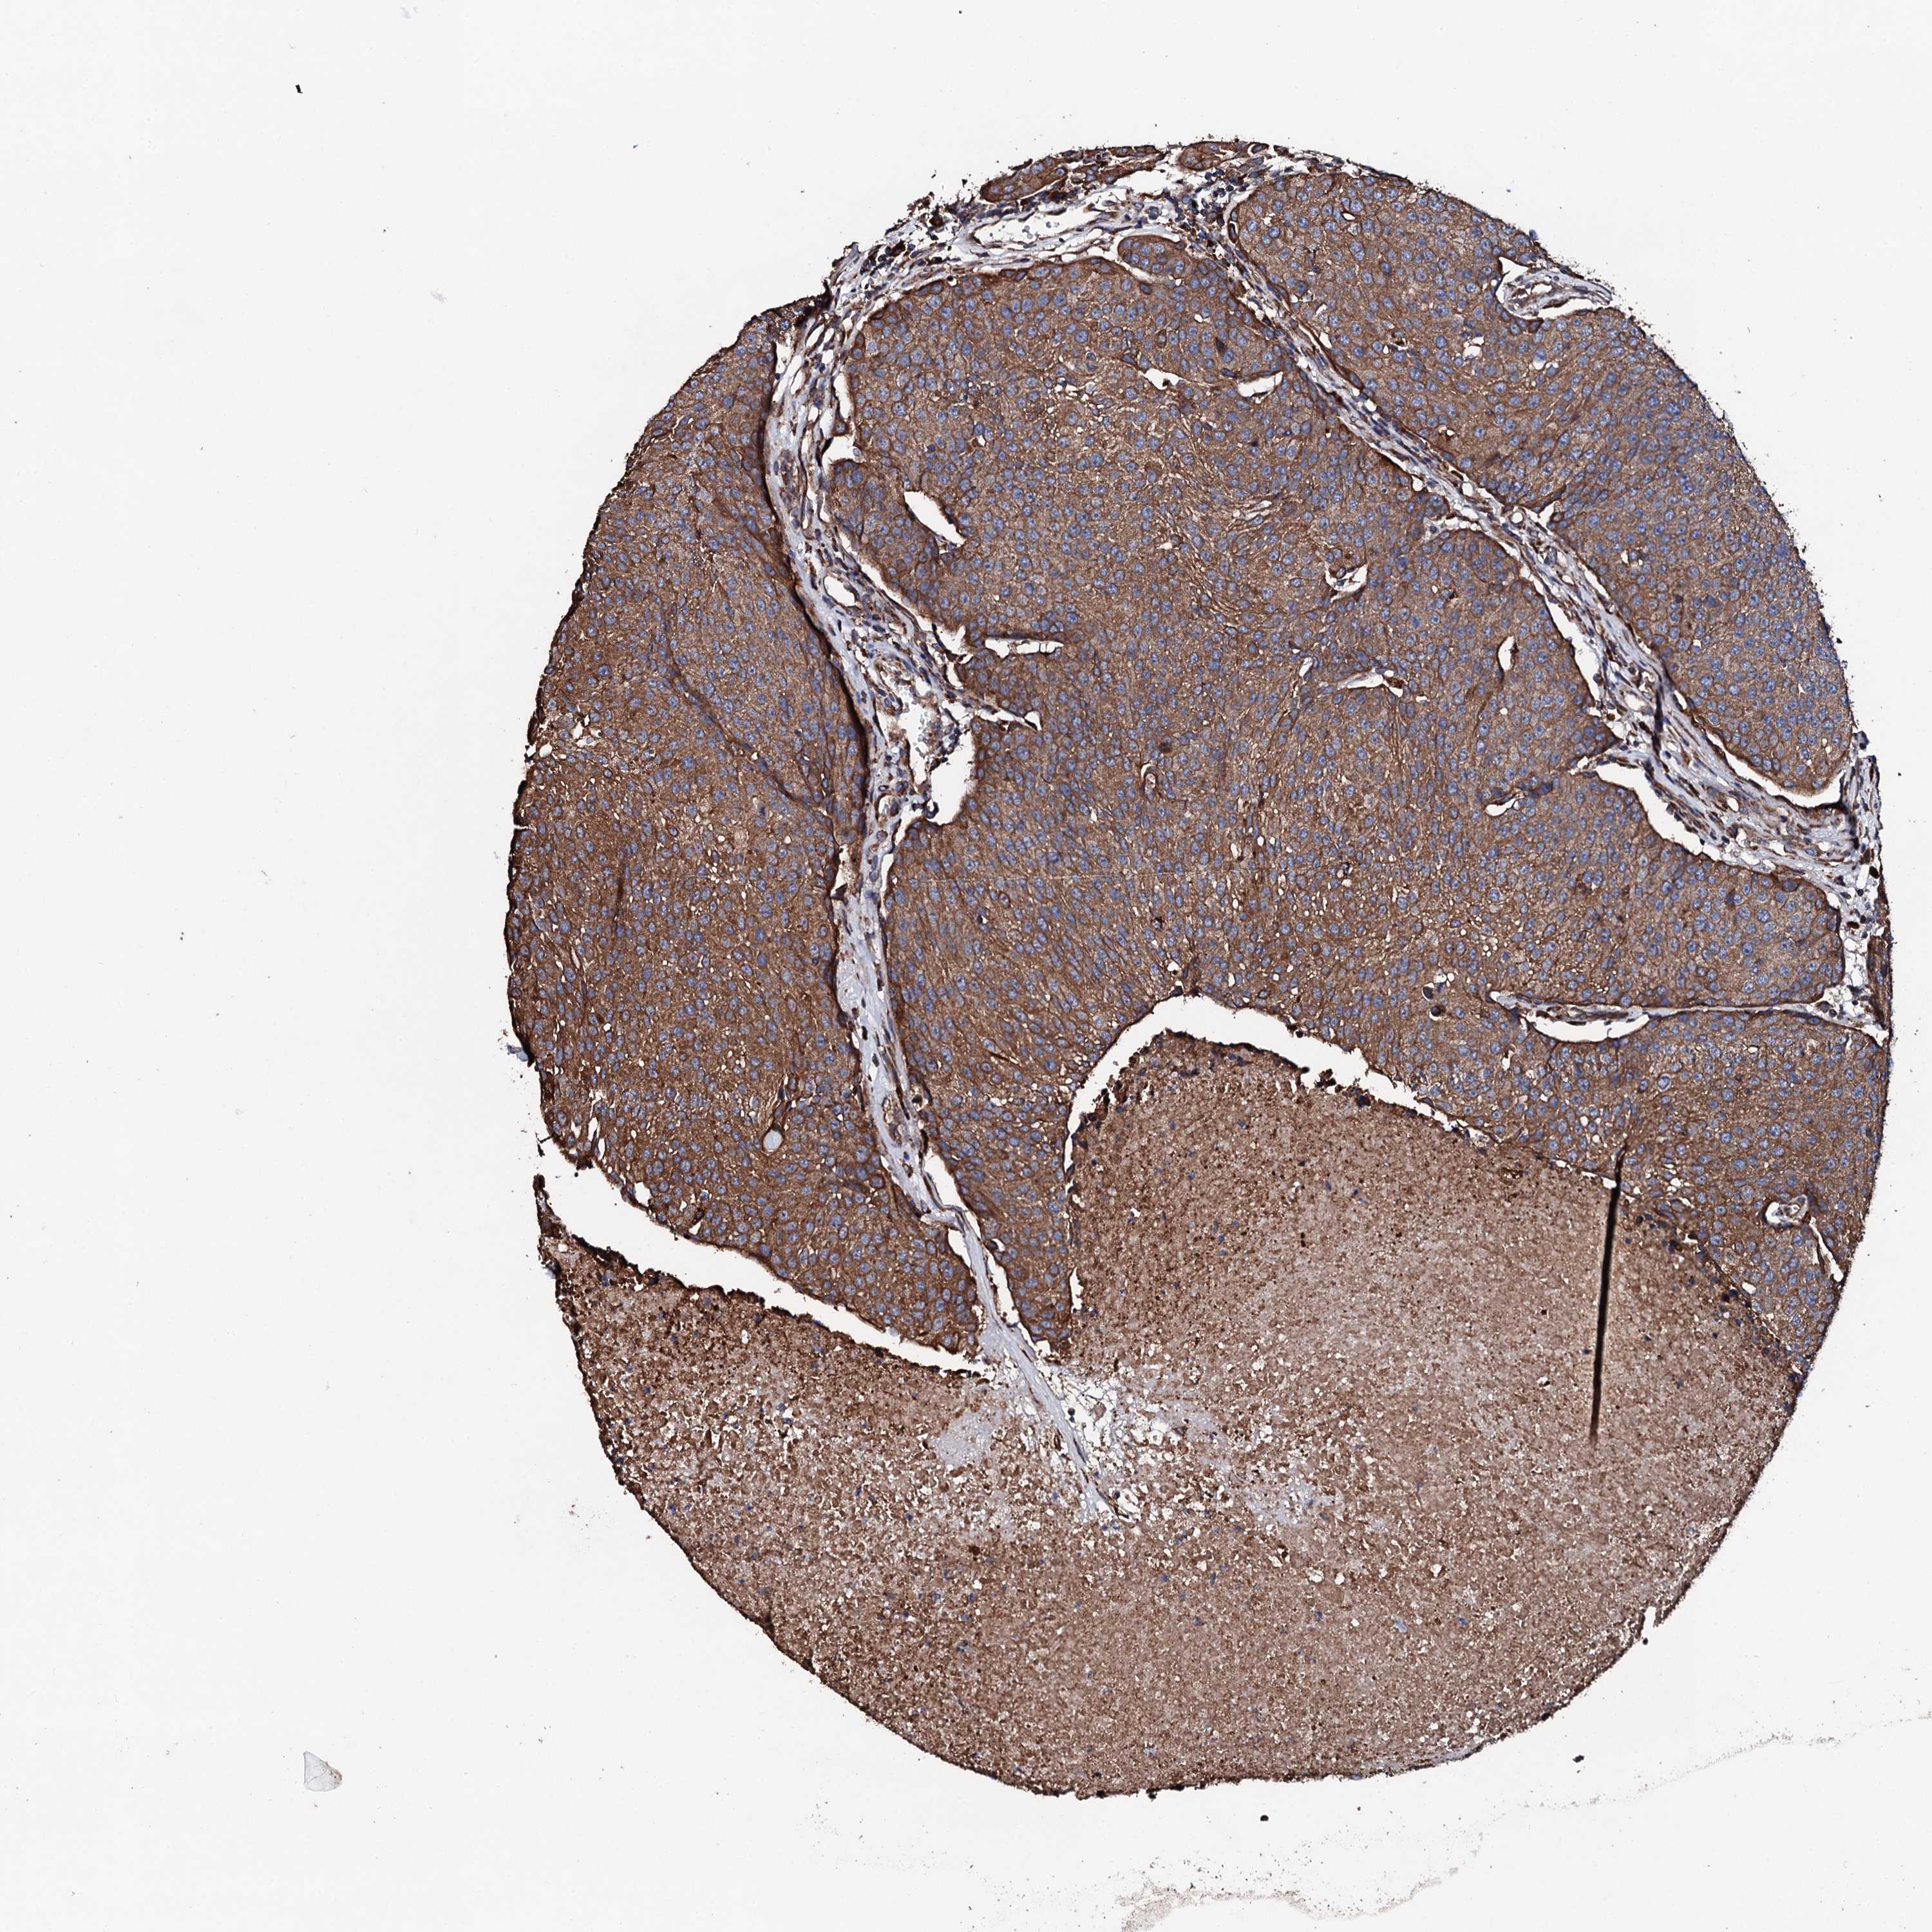

UROTHELIAL CANCER - Protein expressioni

A mouse-over function shows sample information and annotation data. Click on an image to view it in a full screen mode. Samples can be filtered based on level of antibody staining by selecting one or several of the following categories: high, medium, low and not detected. The assay and annotation is described here.

Note that samples used for immunohistochemistry by the Human Protein Atlas do not correspond to samples in the TCGA dataset.

Antibody stainingi

Antibody staining in the annotated cell types in the current human tissue is reported as not detected, low, medium, or high, based on conventional immunohistochemistry profiling in selected tissues. This score is based on the combination of the staining intensity and fraction of stained cells.

Each image is clickable and will lead to virtual microscopy that enables deeper exploration of all samples and also displays staining intensity scores, fraction scores and subcellular localization as well as patient and tissue information for each sample.

Antibody HPA039377

Antibody HPA040375

Urothelial carcinoma, High grade

Urothelial carcinoma, Low grade